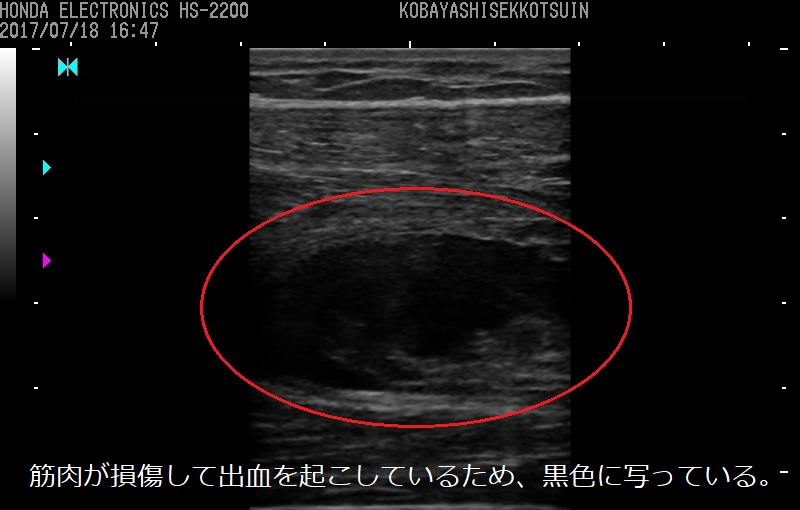

1.損傷した筋肉を触ったり動かしたり、エコーで観察して肉離れした筋肉の状態を把握する

肉離れは損傷程度によって治療方法や治療期間、スポーツ復帰までのリハビリ期間が変わるため、損傷程度をしっかり把握することはとても重要になります。

エコーで筋肉の状態を観察したり、実際に筋肉を触ったり、動かしたりして、エコーの画像も合わせて総合的に肉離れの損傷程度を把握します。